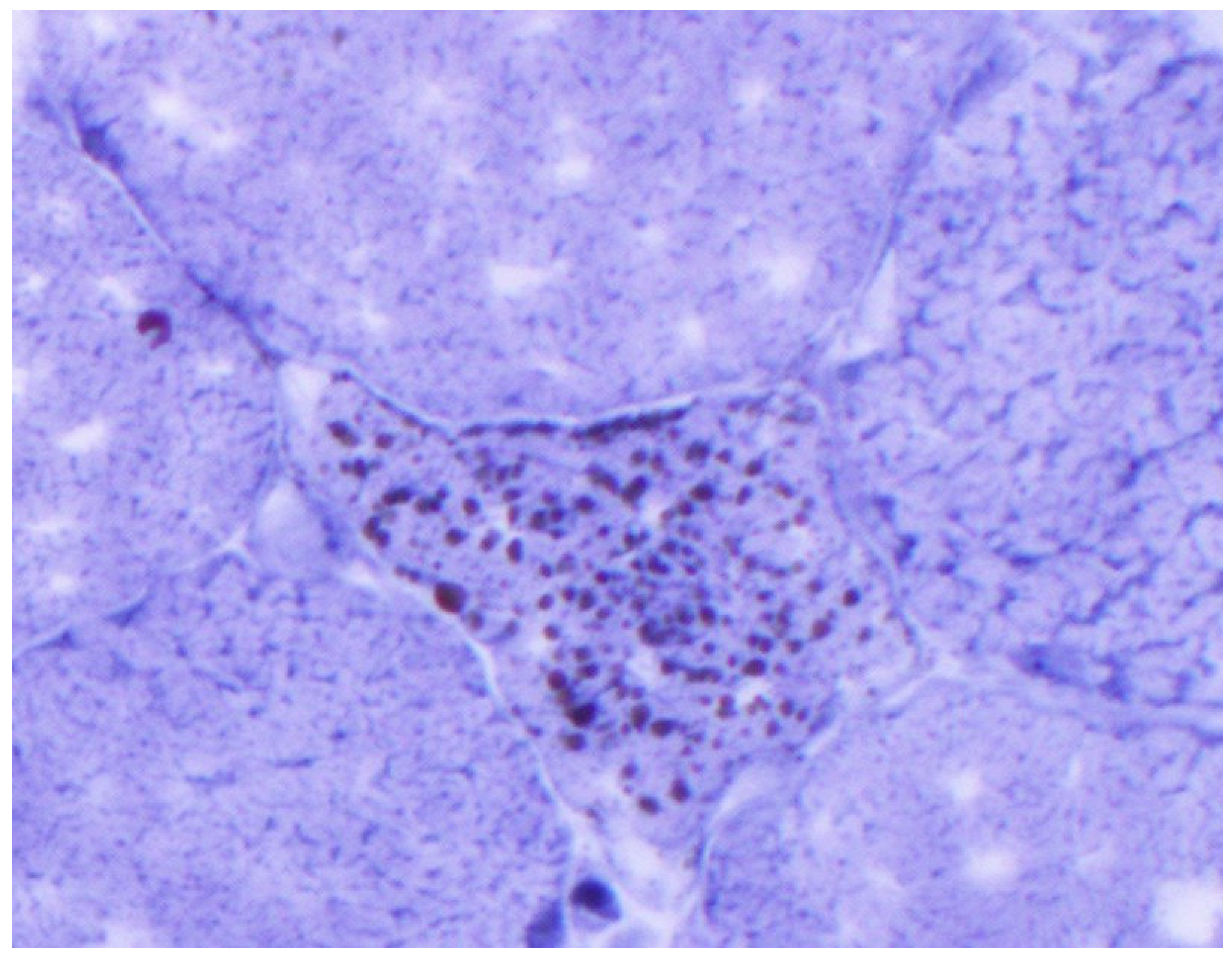

Figure 3.

Sudan black stain: lipid droplets in scattered and intact myofiber (low power).